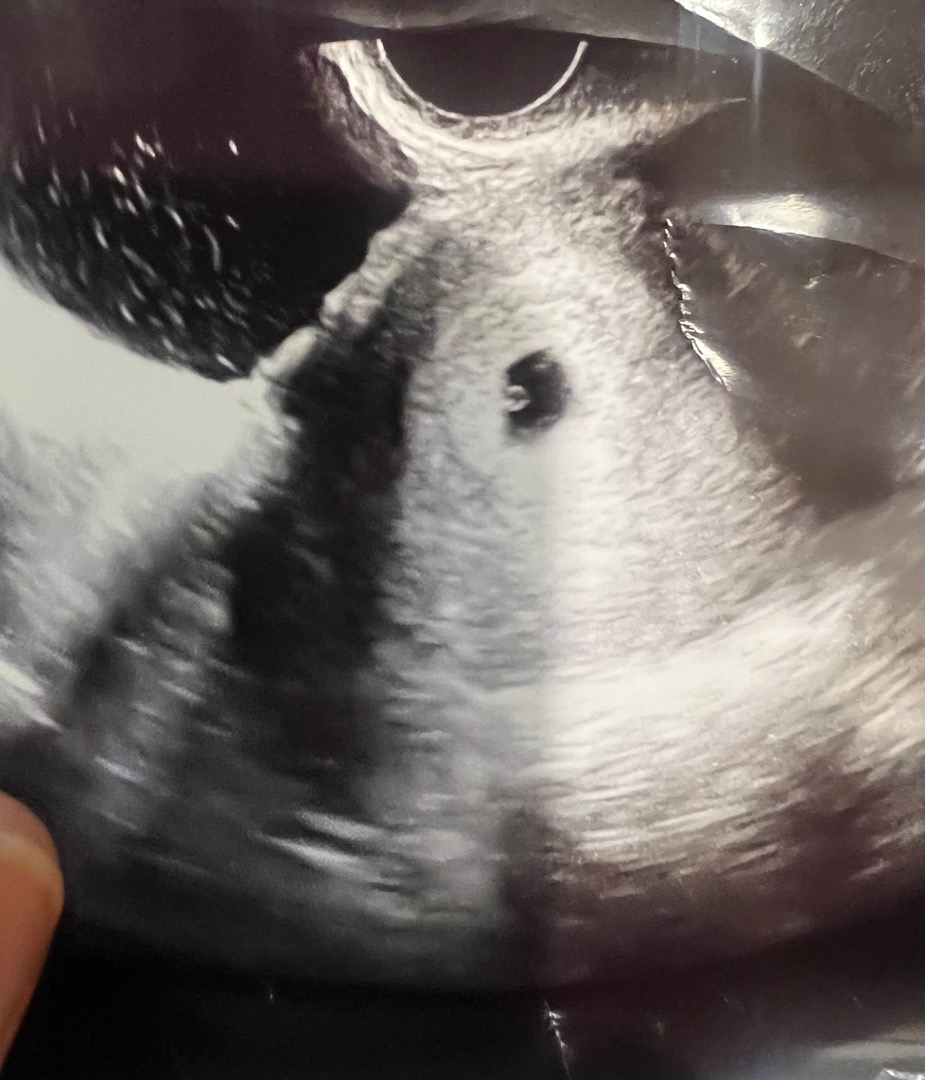

셤관 동결로 했는데 오늘 아기집 난황 봤는데 생리끝물일때처럼 갈색분비물이 하루종일 묻어나네요ㅠ 1차때 계류유산으로 소파술 해서 그런지 계속 신경쓰이네요 ㅠ 5주1일이라 난황은 기대도 안했는데 동그란게 이쁘게 있어서 감동 ㅠㅠ

저도 5주1일 오늘 난황보고 왔어요! 저희 같이 긍정적인 생각만해요😊